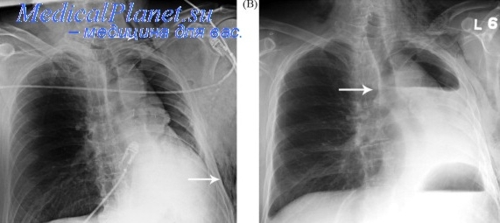

Помимо опроса и объективного осмотра, включающего перкуссию и аускультацию грудной клетки, проводят рентгенологическое исследование в двух положениях тела (в 2-х проекциях). Это основной метод обнаружения ателектазов легких.

На рентгеновских снимках выявляют следующие признаки, указывающие на спадение легочной ткани:

Однородное затемнение в области поражения. Размеры тени зависят от вида ателектаза: при долевом выявляется обширное затемнение, при сегментарном — в виде клина или треугольника, расположенного вершиной к корню легкого, дольковые ателектазы множественные и похожи на очаговую пневмонию. Дистензионный ателектаз расположен низко, около диафрагмы, имеет небольшие размеры и вид поперечных полос или темных дисков. Смещение органов: при компрессионном ателектазе смещение наблюдается в здоровую сторону, так как на стороне поражения давление больше, при обтурационном, наоборот – смещение будет в сторону ателектаза, так как на стороне поражения нарастает притягивающее отрицательное давление. Подъем купола диафрагмы – это видно по расположению печени.

Помимо всего перечисленного выше, рентгеноскопия, то есть исследование «вживую», позволяет увидеть куда смещаются органы в зависимости от фазы дыхания, кашля. Это является дополнительным признаком ателектаза, помогающим выявить тип болезни.

Предварительным, рентгенологическим диагнозом является «синдром правой доли», при котором выявляется затемнение площади средней доли правого легкого.

Частое возникновение ателектаза правого легкого связано с анатомическими особенностями правого среднедолевого бронха: он узкий и длинный, поэтому часто происходит его перекрытие при патологическом процессе.